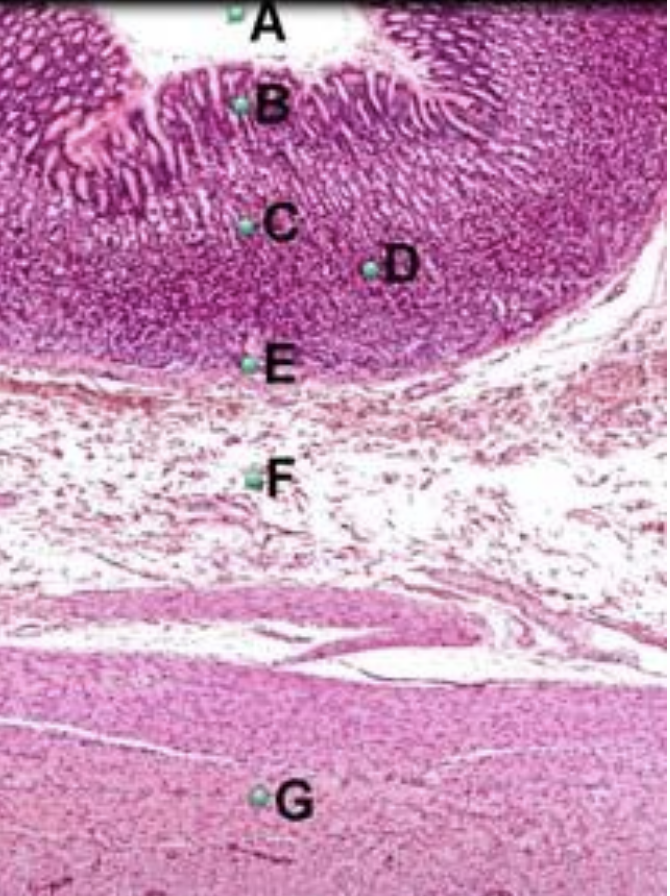

Part A?

opening of gastric pit

Part B?

gastric pit

Part C?

gastric gland

Part D?

muscularis mucosae of stomach